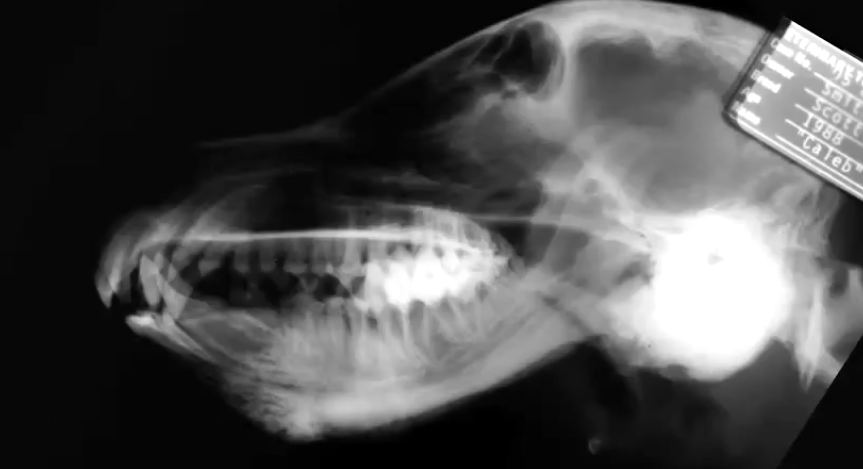

What are the radiographic signs of craniomandibular osteopathy?

Bony proliferation on mandibles, bulla petrous temporal bone, calvarium

Craniomandibular osteopathy